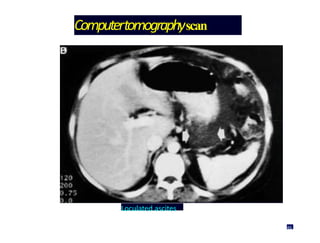

Computertomographyscan

Loculated ascites